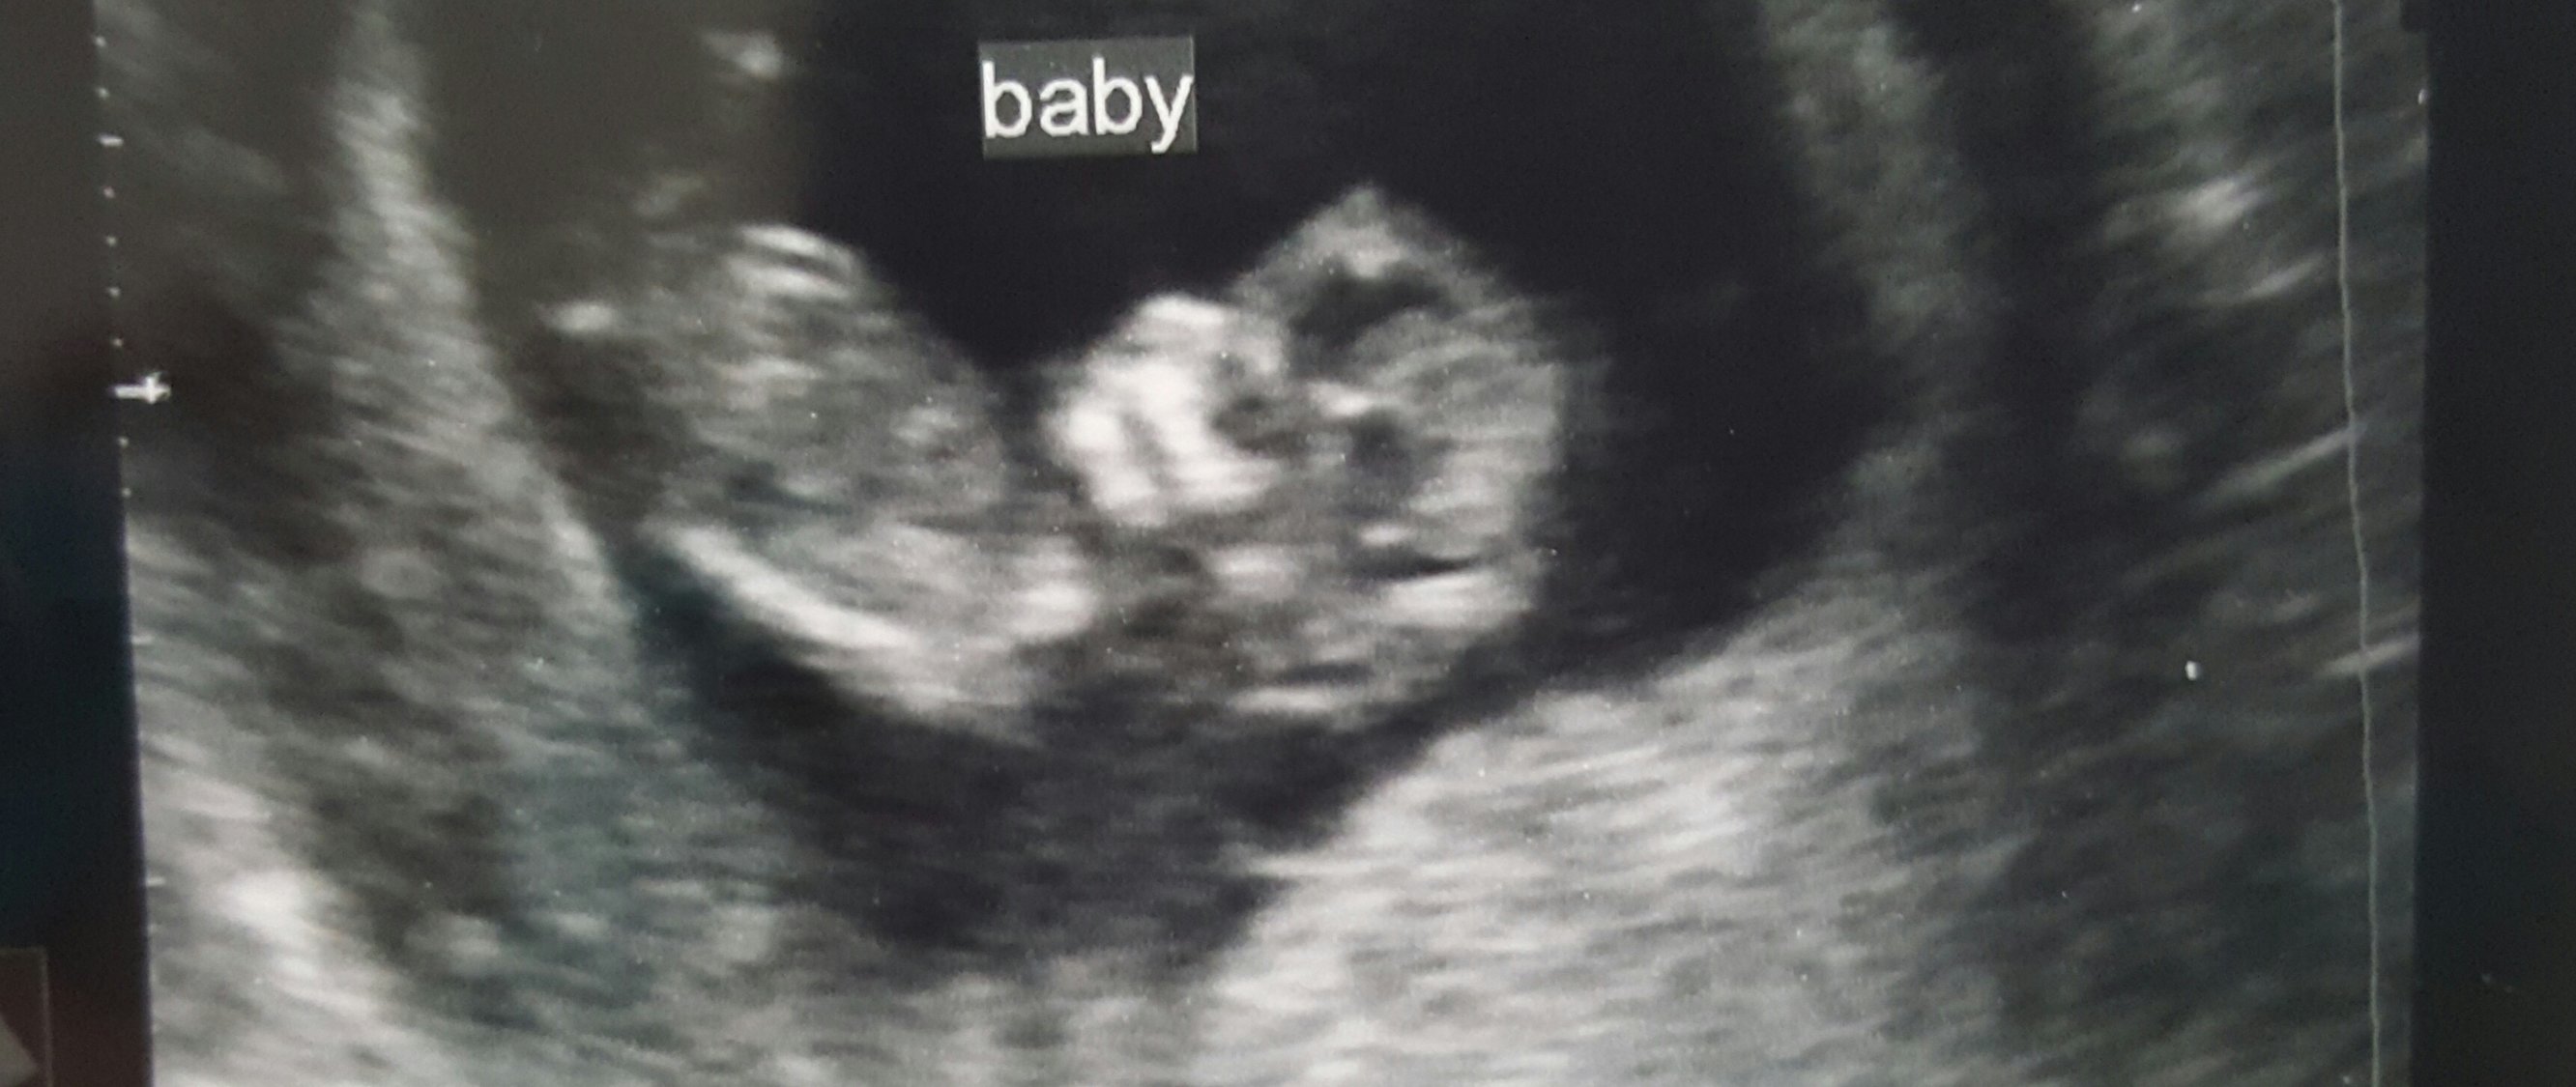

My hubby and me both think we see a little boy part between the legs, our us tech wouldn't say anything other than its too soon (12 weeks) HELP! Do you think it's a boy??? lol